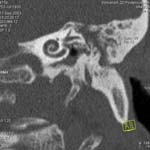

Пример 4. КТ высокого разрешения пирамиды височной кости. Применены тонкие срезы (0.5 мм) и "острый" алгоритм реконструкции (кернель 90).

(Слева) отчетливо видны элементы внутреннего уха - улитка, полукружные канальцы. (В центре) показана проекция продольного сечения височно-нижнечелюстного сустава. (Справа) - холестеатома.